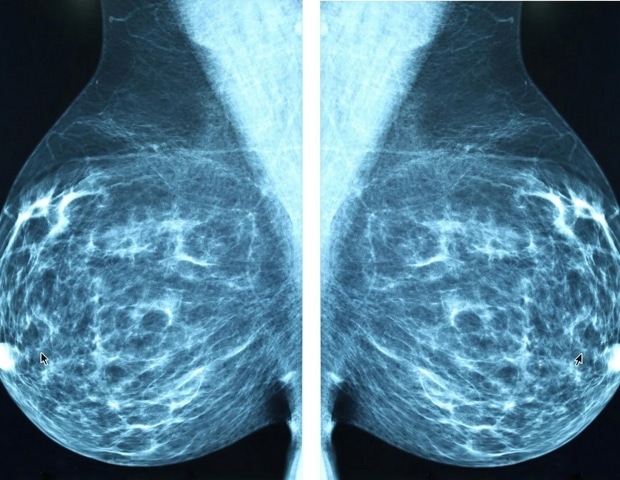

Αύξηση του βάρους του καρκίνου του μαστού στις χώρες χαμηλού εισοδήματος

Παρά τις πρόσφατες προόδους στις θεραπείες του καρκίνου του μαστού, οι νέες περιπτώσεις καρκίνου σε γυναίκες αναμένεται να αυξηθούν κατά ένα τρίτο παγκοσμίως, από 2,3 εκατομμύρια το 2023 σε περισσότερα από 3,5 εκατομμύρια μέχρι το 2050. Ταυτόχρονα, οι ετήσιοι θάνατοι από τη νόσο προβλέπεται να εκτοξευθούν κατά 44%, από περίπου 764.000 σε 1,4 εκατομμύρια, με τις χώρες με περιορισμένους πόρους να πλήττονται ιδιαίτερα, σύμφωνα με μια σημαντική νέα ανάλυση από την Global Burden of Disease Study Breast Cancer Collaborators, που δημοσιεύθηκε στο The Lancet Oncology.

Ο καρκίνος του μαστού παραμένει ο πιο κοινός καρκίνος μεταξύ των γυναικών παγκοσμίως, με εκτιμώμενες 2,3 εκατομμύρια νέες διαγνώσεις το 2023 (με το 73% ή 1,67 εκατομμύρια περιπτώσεις να συμβαίνουν σε χώρες υψηλού και μεσαίου εισοδήματος) και 764.000 θανάτους (με το 39% ή 300.000 θανάτους να καταγράφονται σε χώρες χαμηλού και μεσαίου εισοδήματος).